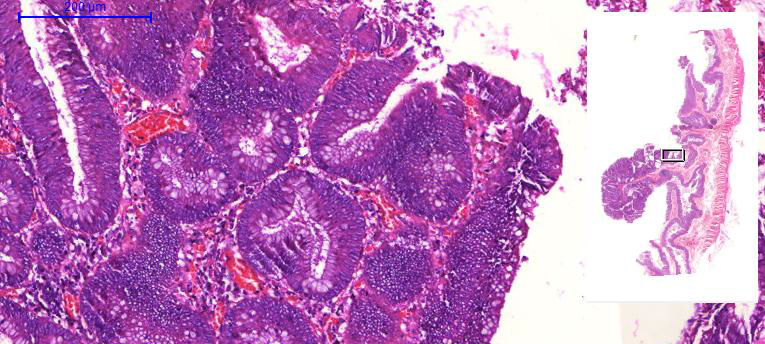

2. Adenocarcinoma tubular (A526)

1. Desorganização arquitetural

1. Reação desmoplásica próxima ao tumor

1. Invasão da submucosa